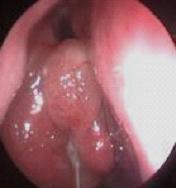

鼻炎长期得不到有效治疗导致鼻息肉以及鼻腔囊肿